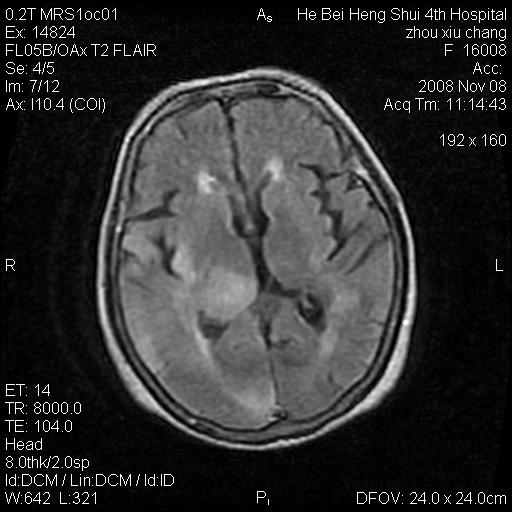

标题: MRI1883:女67岁,半年前曾患脑梗塞,治疗后好转,近3各月精

女67岁,半年前曾患脑梗塞,治疗后好转,近3各月精神恍惚。

形态及整体病灶看起来首先考虑转移瘤或淋巴瘤,但奇怪的是多个病灶周围均未见显著的水肿区,这不符合这两个肿瘤的特点,结合ct表现及患者病史有个人考虑是否有皮层下动脉硬化性脑病伴多发胶质增生可能.